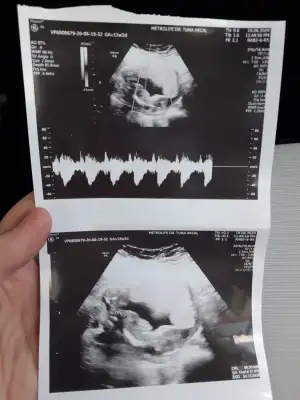

12. Haftada tahmin eden çok olmuyor. Benimki bi tahminde bulundu ama 16. Haftada netleşecek.Doktor bir tahminde bulunmuyor mu?

Sanki yine kız gibi

Doktorda kız gibi dedi sağ ol canım kesinleşince yazarım❤Sanki yine kız gibi![]()

Kız sanki emin olmadım çok net değil usg varsa 11 yada 13 hafta usg olursa paylaşınSelam canlar, anlayan varsa bize de bakabilir mi acaba![]()

Doktorda kız dedi zaten 11+5 de gıttım buna daha yeni canım :) obur ay gıderım bide. Teşekkür ederim tatlımKız sanki emin olmadım çok net değil usg varsa 11 yada 13 hafta usg olursa paylaşın![]()